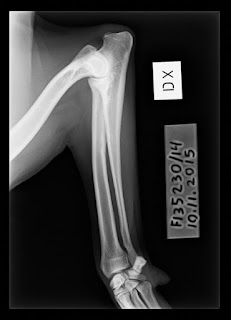

| Kyynär 0 |